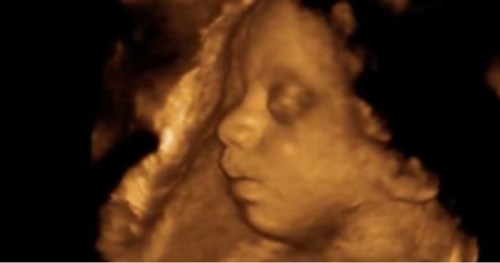

ABORTION: [3:04] – Video from the first Red Rose Rescue since FAUXTUS took office. One Catholic priest, Father Fidelis Moscinski, CFR, was arrested along with Lauren Handy and Jonathan Darnell for entering the facility, offering roses to the mothers inside, and refusing to leave.

HONDURAS: The Honduran National Congress strengthened pro-life laws last week by amending the national constitution to declare that unborn babies have the same rights as born human beings under the law.